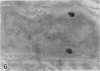

Abundant inflammatory cells such as polymorphonuclear leucocytes and macrophages accumulated and adhered to the endothelial surface of glomerular and intertubular veins and capillaries in rat kidneys after administration of bacterial lipopolysaccharide (LPS). There was also damage to both endothelial cells and proximal tubular cells, including intracytoplasmic oedema, and an increase in the number of lysosomes in the proximal tubular cells in the LPS-treated samples. Immunocytochemistry was used to demonstrate tumour necrosis factor (TNF) and leukotriene (LTR) in both LPS-treated and control samples. Immunoreactive LTR seen in the lysosomes of inflammatory cells attached to the endothelial cell surface may indicate the onset of endothelial cell damage. Positive immunoreactive TNF and LTR were seen on the endothelial cell surface only in the LPS-treated samples, indicating that TNF and LTR may enhance the adhesion of leucocytes to endothelium. Positive reactions of TNF and LTR in lysosomes of the mesangial cells suggest that lysosomes of such cells may be involved in the synthesis and storage of TNF and LTR. In addition to these reaction sites, lysosomes of proximal tubular cells were immunoreactive for LTR. These endogenous LTRs may be implicated in the degeneration of the proximal tubular cells.